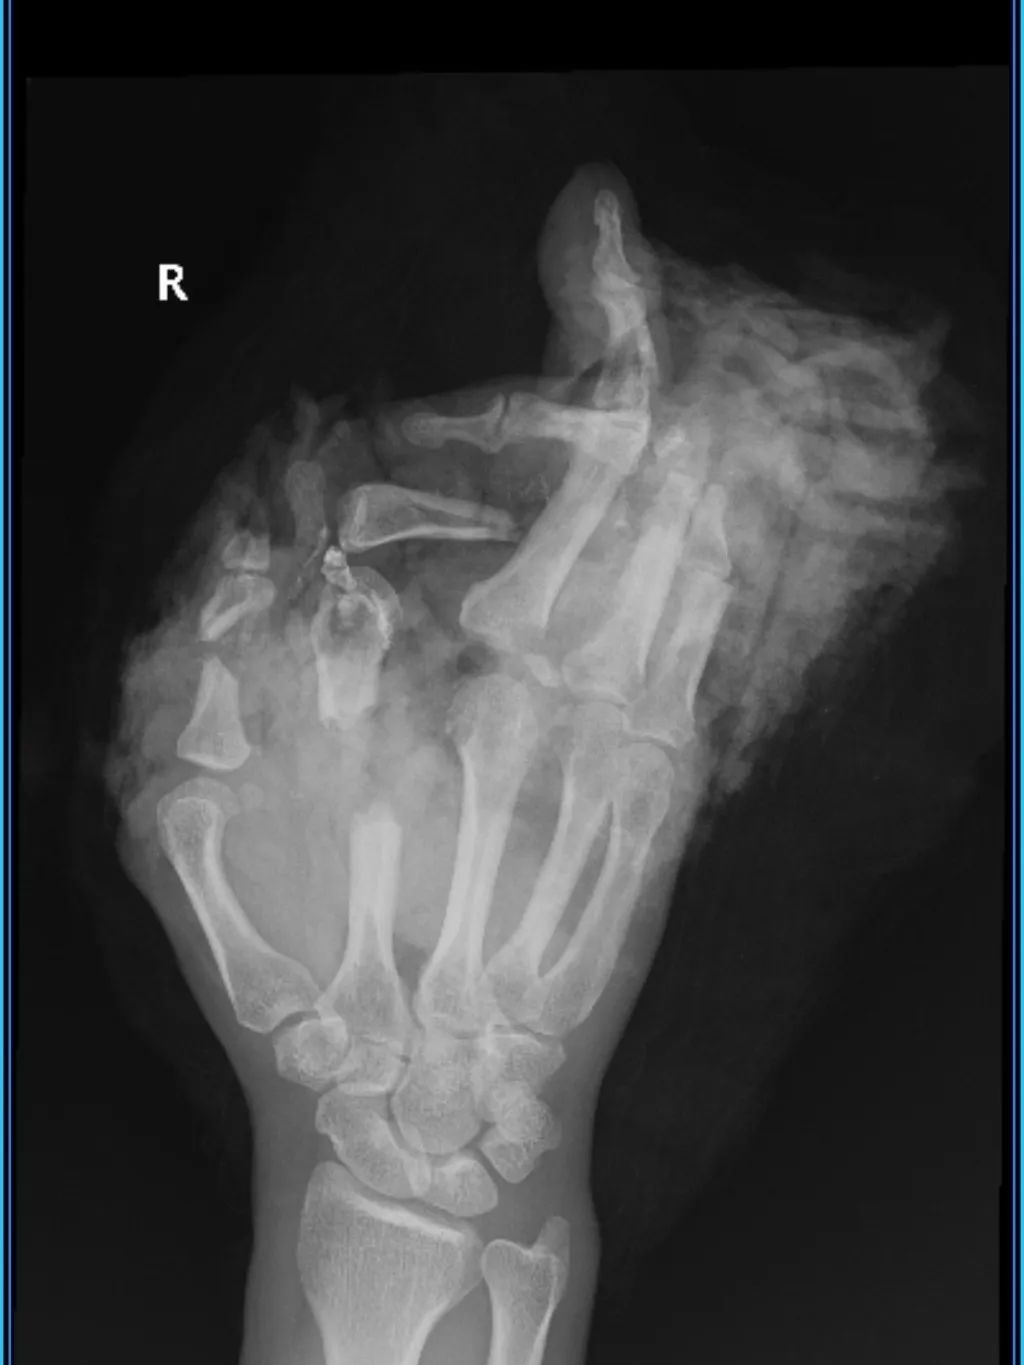

绞肉机拆除工作好不容易完成了。患者右手掌至右手指呈现毁损畸形状况。这一状况非常惨烈。之后。在医护人员严密监护下。患者被专业护送。迅速转移至放射科。去进行进一步影像学检查。

放射科检查有了结果。右手X片显示出相关状况。右手第2、3掌指关节脱位。第2、4掌骨有毁损伤。第1至5指也存在毁损伤。部分骨质严重缺损。周围软组织也严重缺损。情况严重,令人担忧。